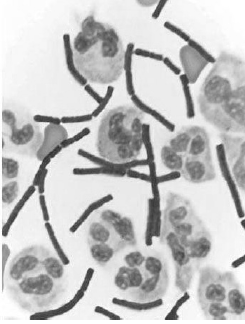

A figura precedente mostra o fluido cérebro-espinhal de um paciente com infecção bacteriana. Considerando essa informação e os múltiplos aspectos a ela relacionados, julgue o item a seguir.

Antraz, doença que já foi explorada como arma biológica, é causada por uma bactéria que apresenta a forma do microrganismo mostrado na figura.

Considerando-se a forma da bactéria e o fato de ela estar presente no fluido cérebro-espinhal, deve-se realizar prova de Gram nessa amostra para a confirmação da infecção por Neisseria meningitidis.

Bactérias que têm a mesma forma das apresentadas nessa figura podem ser transmitidas por inalação, ingestão ou por via cutânea.

De acordo com a figura, o fluido cérebro-espinhal desse paciente contém acúmulo de células imunológicas mononucleares.

A figura mostra que o paciente possui infecção por bactérias espirilos.